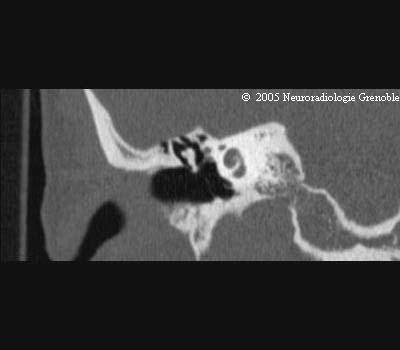

Radioanatomie TDM du rocher normal

Cochlée

Tympan

Conduit auditif externe

Marteau

Canal du facial

Canal du muscle du marteau